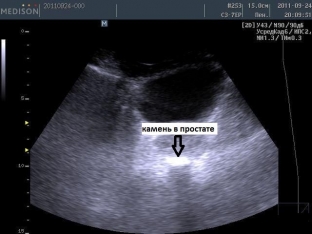

The diagnostic process of stones in the prostate gland is based on the data of digital rectal examination and instrumental diagnostic methods. During palpation of the prostate gland, the stones in it are determined in the form of strong formations; if they are close to each other, crepitus may be noted during palpation. Plain x-ray shows dense shadows behind or above the pubic symphysis. Informative is also an ultrasound examination of the prostate with a filled bladder, which allows you to accurately determine the size, number and location of stones. Stones on ultrasound are defined as clear echopositive prostate masses with acoustic shadowing.